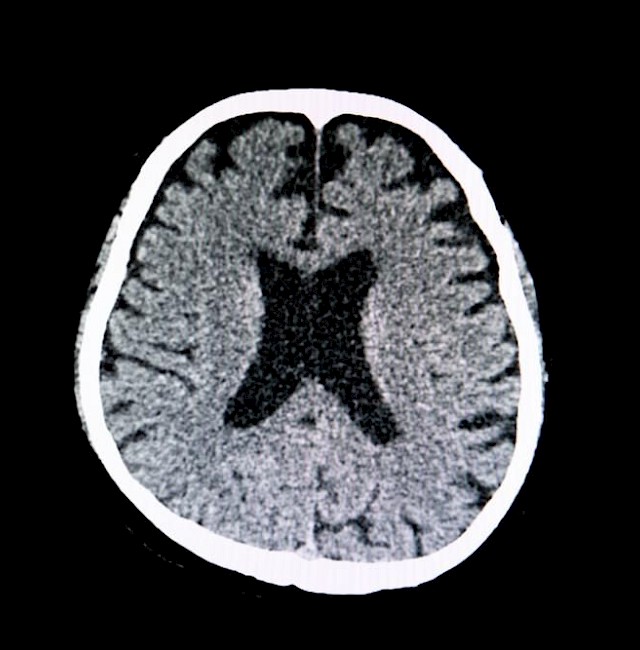

A daganatos megbetegedések kezelésénél létfontosságú, hogy a problémát mihamarabb észrevegyék. Ehhez az orvosoknak többféle vizsgálatot kell elvégezniük. Létezik viszont egy egyszerű módszer, mellyel észlelni lehet a rák számos típusának a korai jeleit. Alábbi cikkünkben erről a tesztről beszélünk.

Egy vizsgálattal könnyen felismerhetők a rák korai jelei